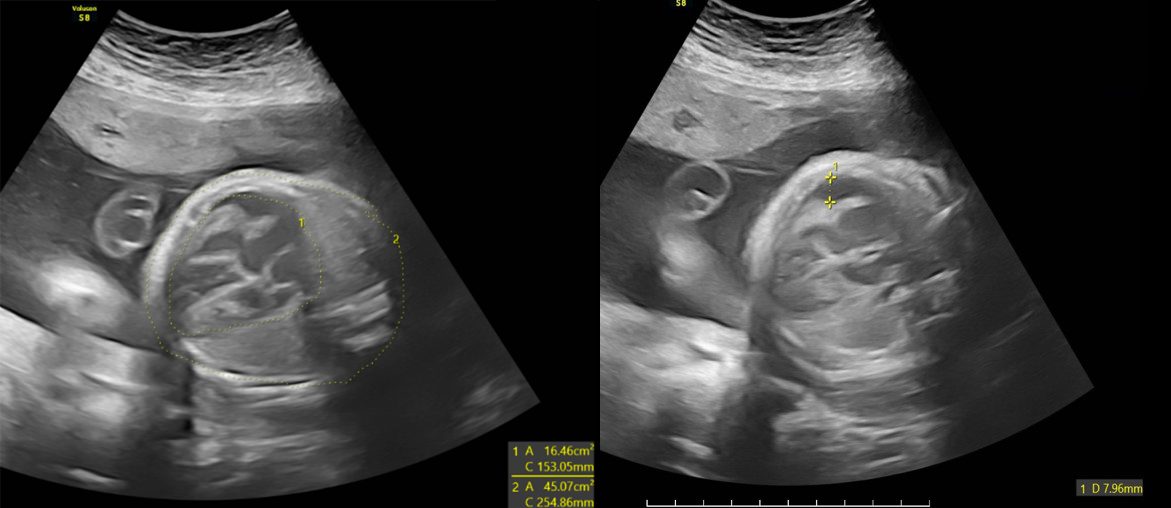

Chị P., 24 tuổi, đến Phòng khám Đa khoa MEDLATEC Thanh Xuân để siêu âm thai định kỳ. Tại đây, với hệ thống thiết bị hiện đại cùng đội ngũ bác sỹ giàu kinh nghiệm, hàng loạt bất thường nghiêm trọng ở thai nhi đã được phát hiện.

| Các bất thường ở thai nhi được phát hiện trên hình ảnh siêu âm |

Hình ảnh siêu âm cho thấy tim thai to bất thường, kèm theo dịch màng ngoài tim, dấu hiệu cảnh báo nguy cơ suy tim hoặc rối loạn tuần hoàn.

Gan và lách của thai nhi cũng tăng kích thước rõ rệt, cho thấy tình trạng viêm hoặc rối loạn chức năng cơ quan. Đáng lo ngại hơn, não thất hai bên giãn rộng kèm giãn hố sau, là biểu hiện tổn thương não nghiêm trọng, có thể dẫn đến chậm phát triển trí tuệ, động kinh hoặc các di chứng thần kinh nặng nề sau sinh.

Trước những bất thường này, thai phụ được chỉ định chọc ối làm xét nghiệm PCR. Kết quả xác định thai nhi dương tính với virus CMV, chẩn đoán nhiễm CMV bẩm sinh.

BSCKI Trần Thế Quỳnh, chuyên khoa chẩn đoán hình ảnh, người trực tiếp thực hiện siêu âm, đã thông báo và giải thích chi tiết cho thai phụ về từng dấu hiệu bất thường cũng như tiên lượng nặng của bệnh.

Các kết quả hội chẩn với tuyến trên cho thấy nguy cơ cao thai nhi có thể đối mặt với những biến chứng nghiêm trọng như bại não, điếc bẩm sinh và nhiều rối loạn thần kinh khác. Trước tiên lượng xấu, thai phụ được chỉ định đình chỉ thai kỳ.